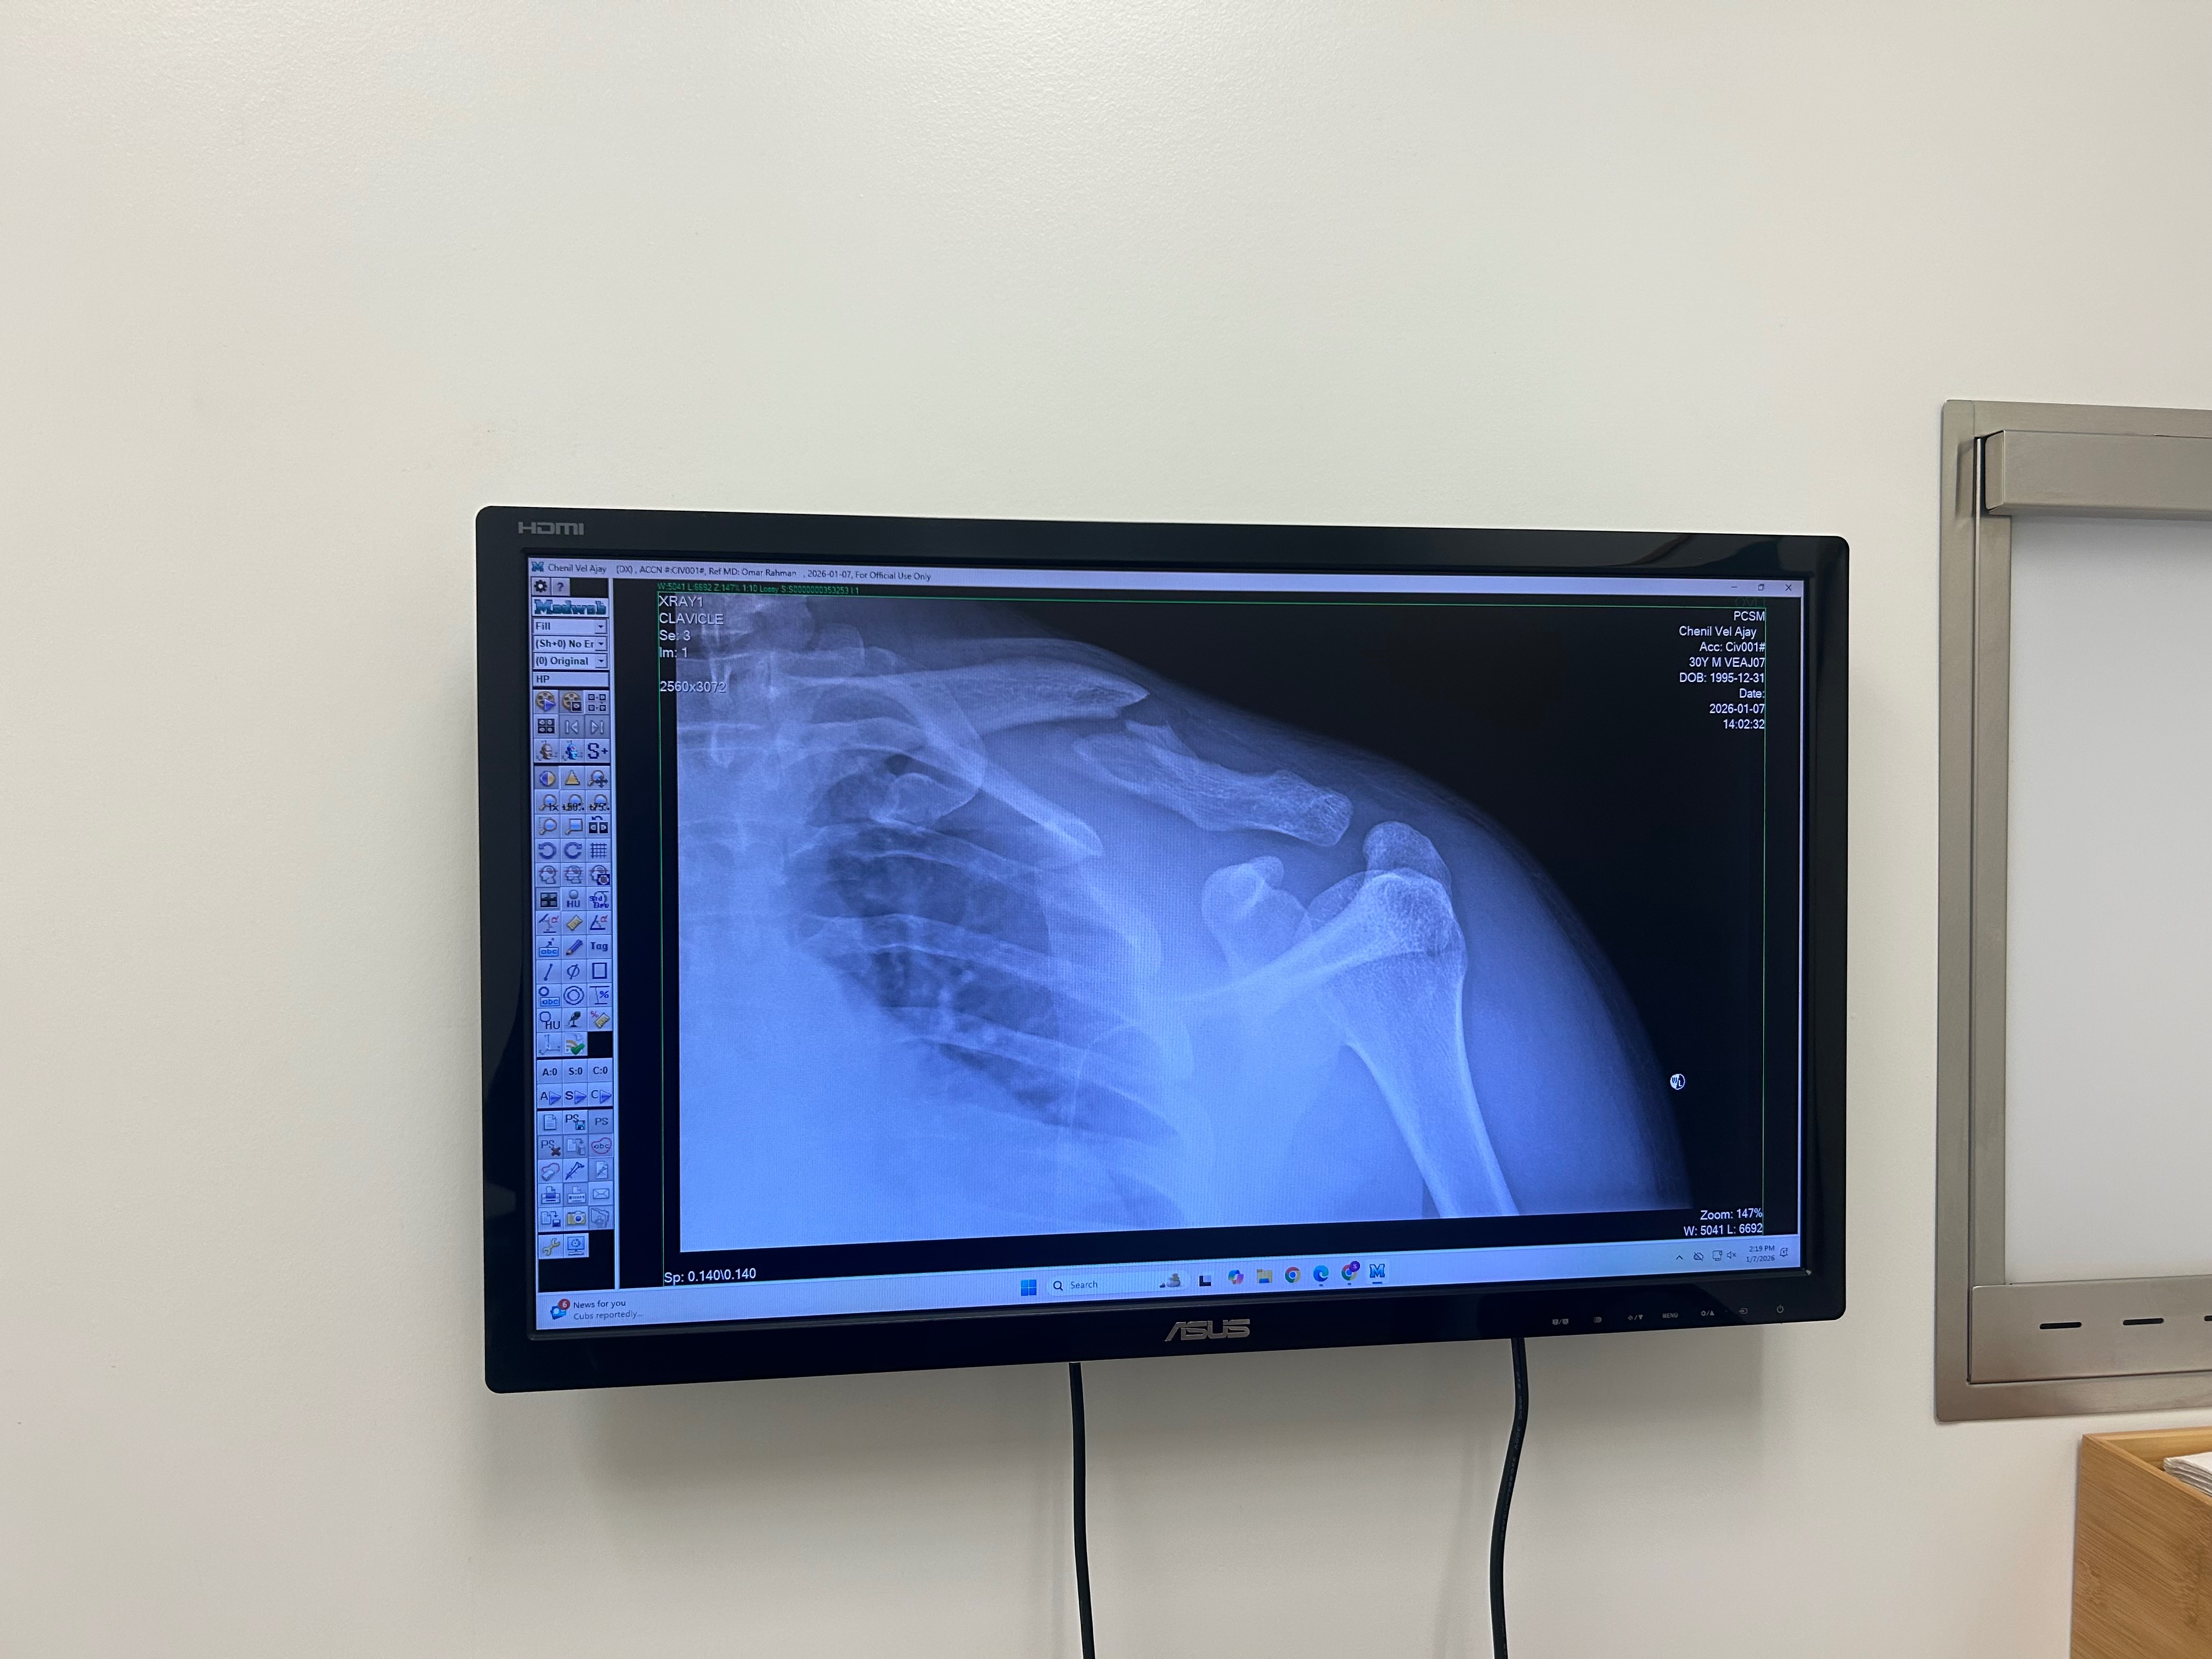

On December 29th, my life took an unexpected turn when I was hit by a car while riding a Lime scooter. The accident left me with a broken clavicle and significant bruising on my hips and legs. As a result, I need surgery on my collar bone and have been unable to attend work. Not having health insurance has made this situation even more challenging, as the medical bills and daily living expenses are quickly adding up.